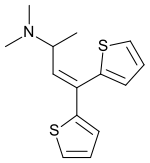

Thiambutenes

Structures